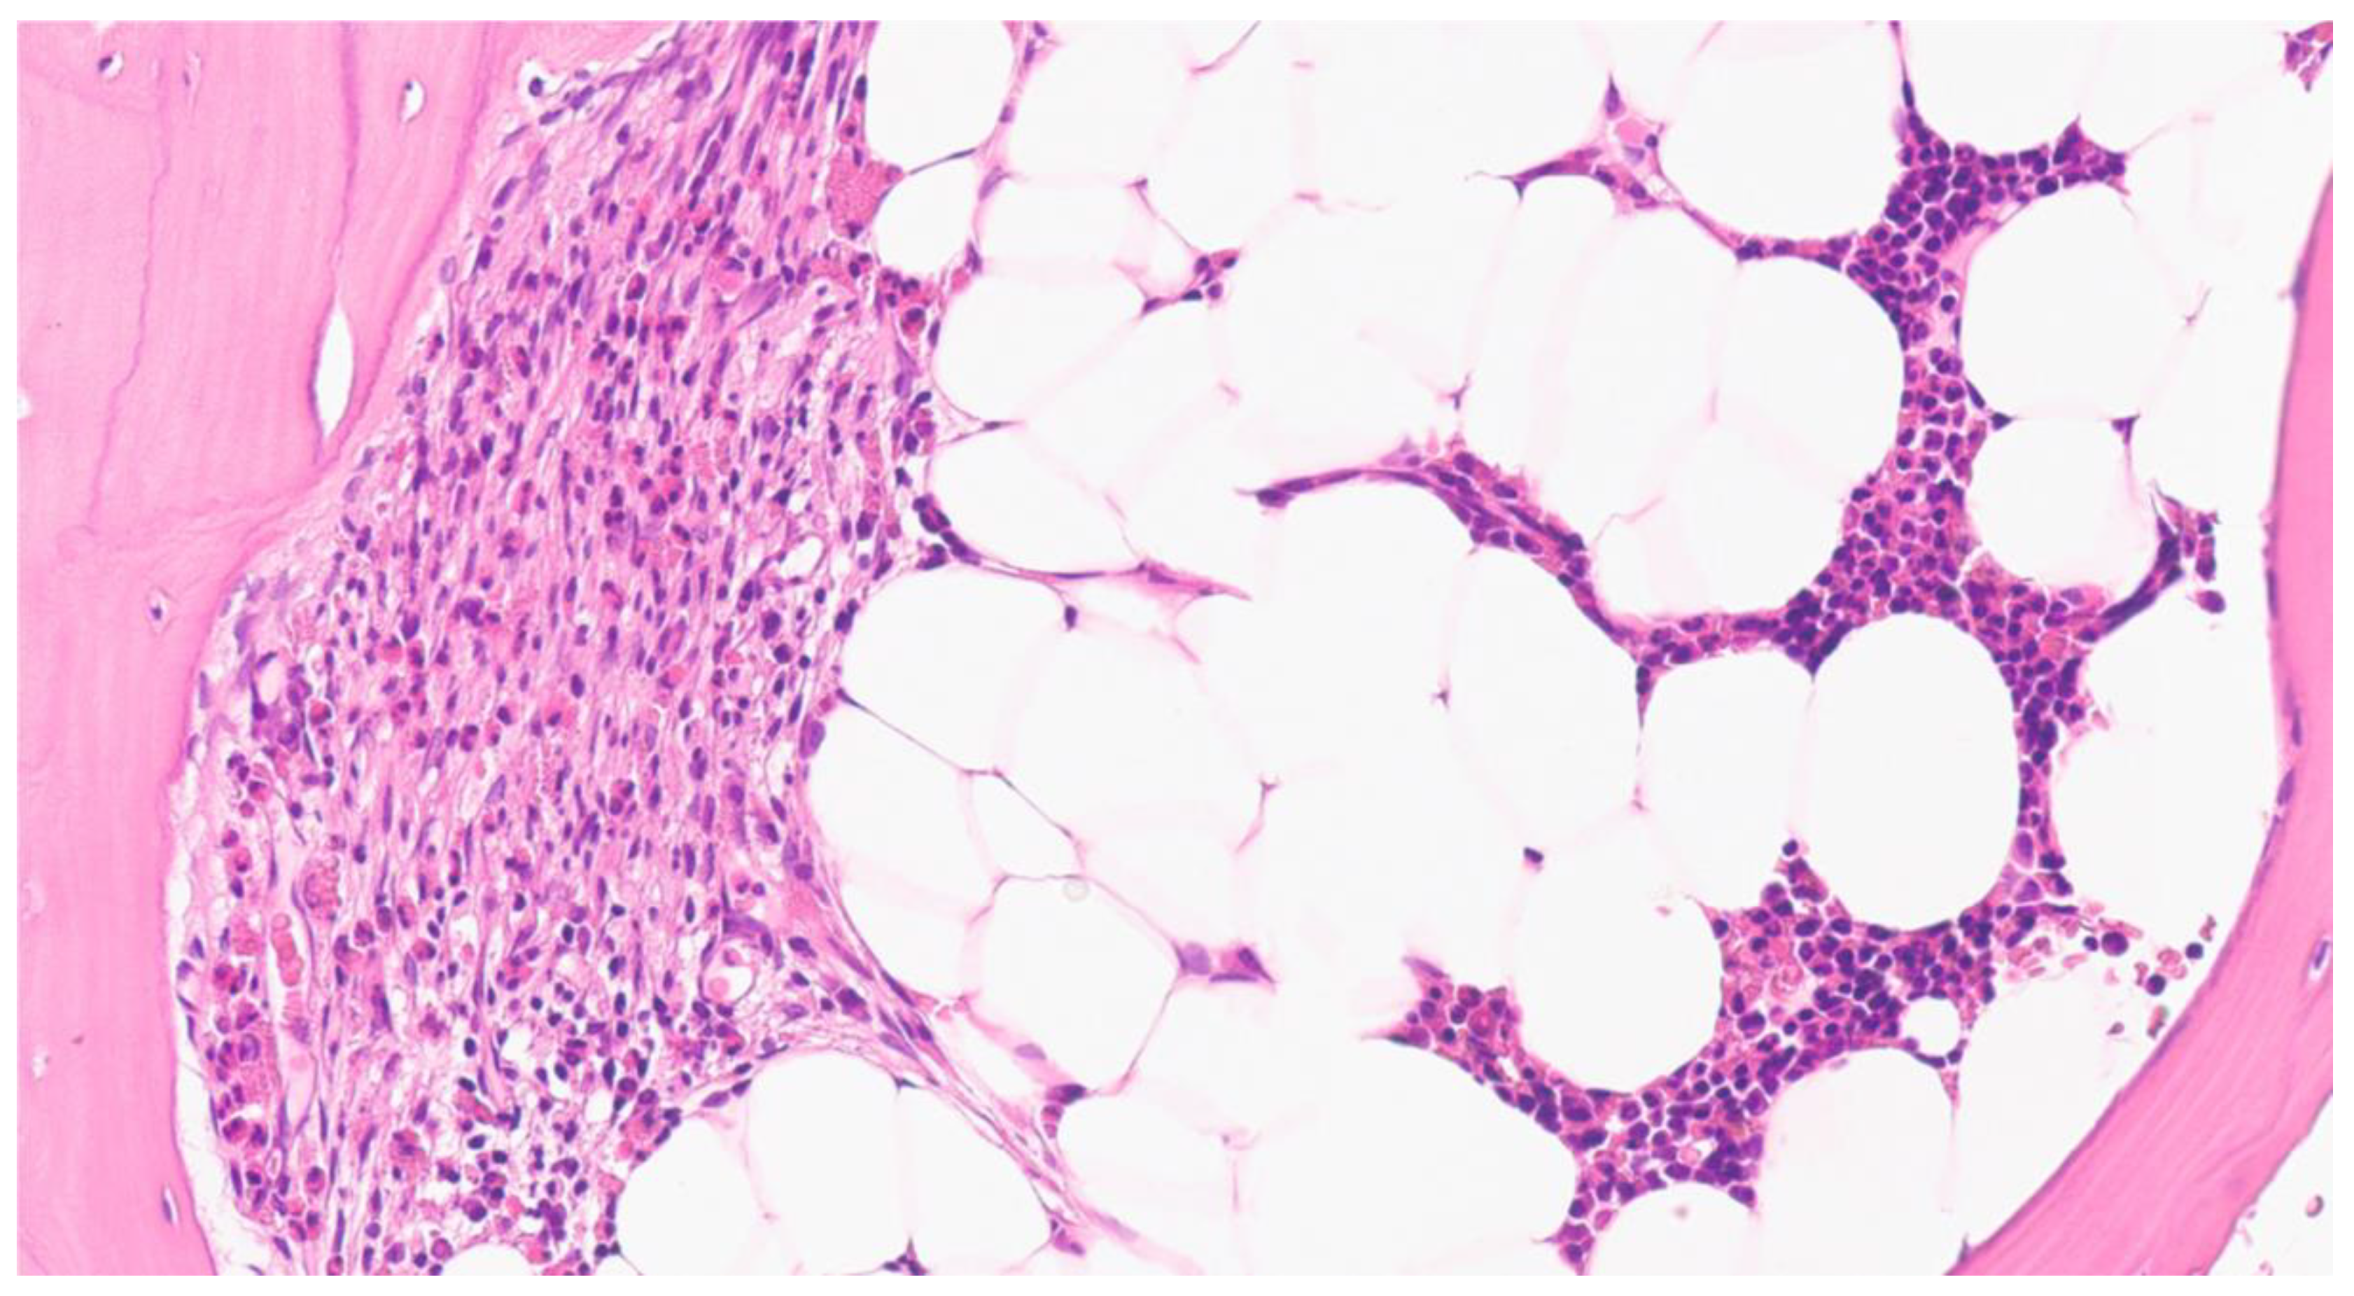

2. Results

2.1. Case 1

2.2. Case 2

2.3. Case 3

2.4. Case 4